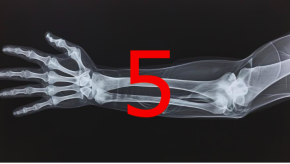

b/ts-DMARDs Do Not Arrest Bone Loss in RA

In RA, the goal is to control or arrest inflammation such that articular and bony damage is halted. While we have many effective therapies, it is not clear that biologic or targeted synthetic disease-modifying antirheumatic drugs (b/tsDMARDs) can prevent or improve osteoporosis outcomes in RA. A